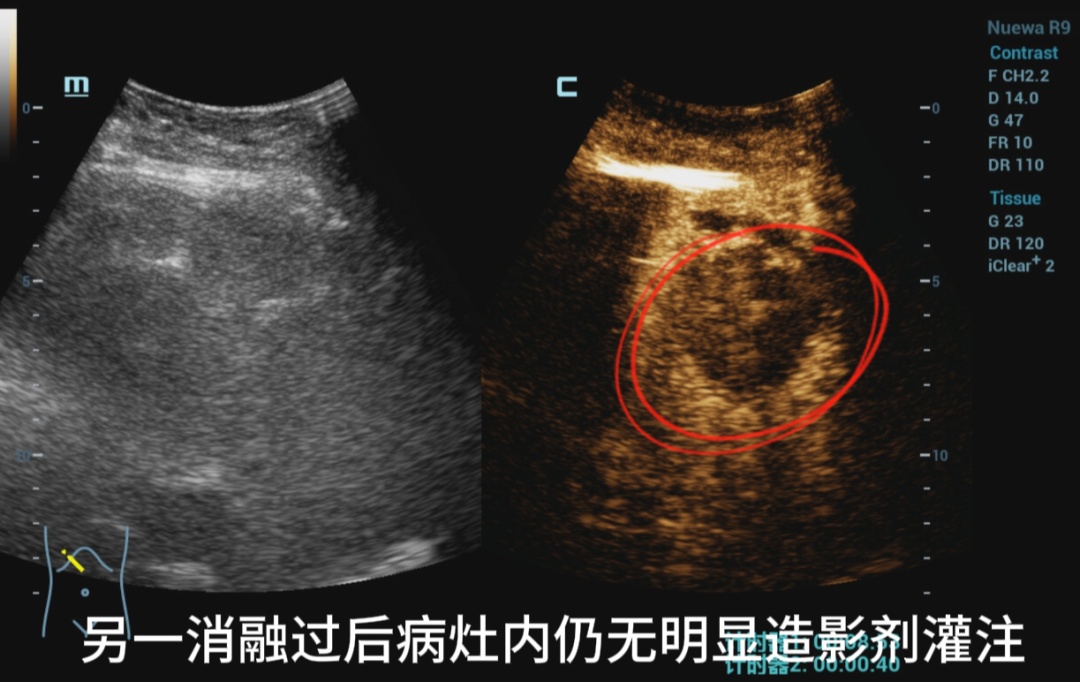

消融过后即刻打造影剂

评估消融效果

IVa段病灶

两病灶内均无明显造影剂灌注,消融效果满意。

患者出院前超声造影复查

复查结果提示未见肝内有强化病灶,肿瘤完全失去了活性。经外周静脉注射造影剂Sonazoid后,病灶区域始终未灌注区,显示消融效果满意。